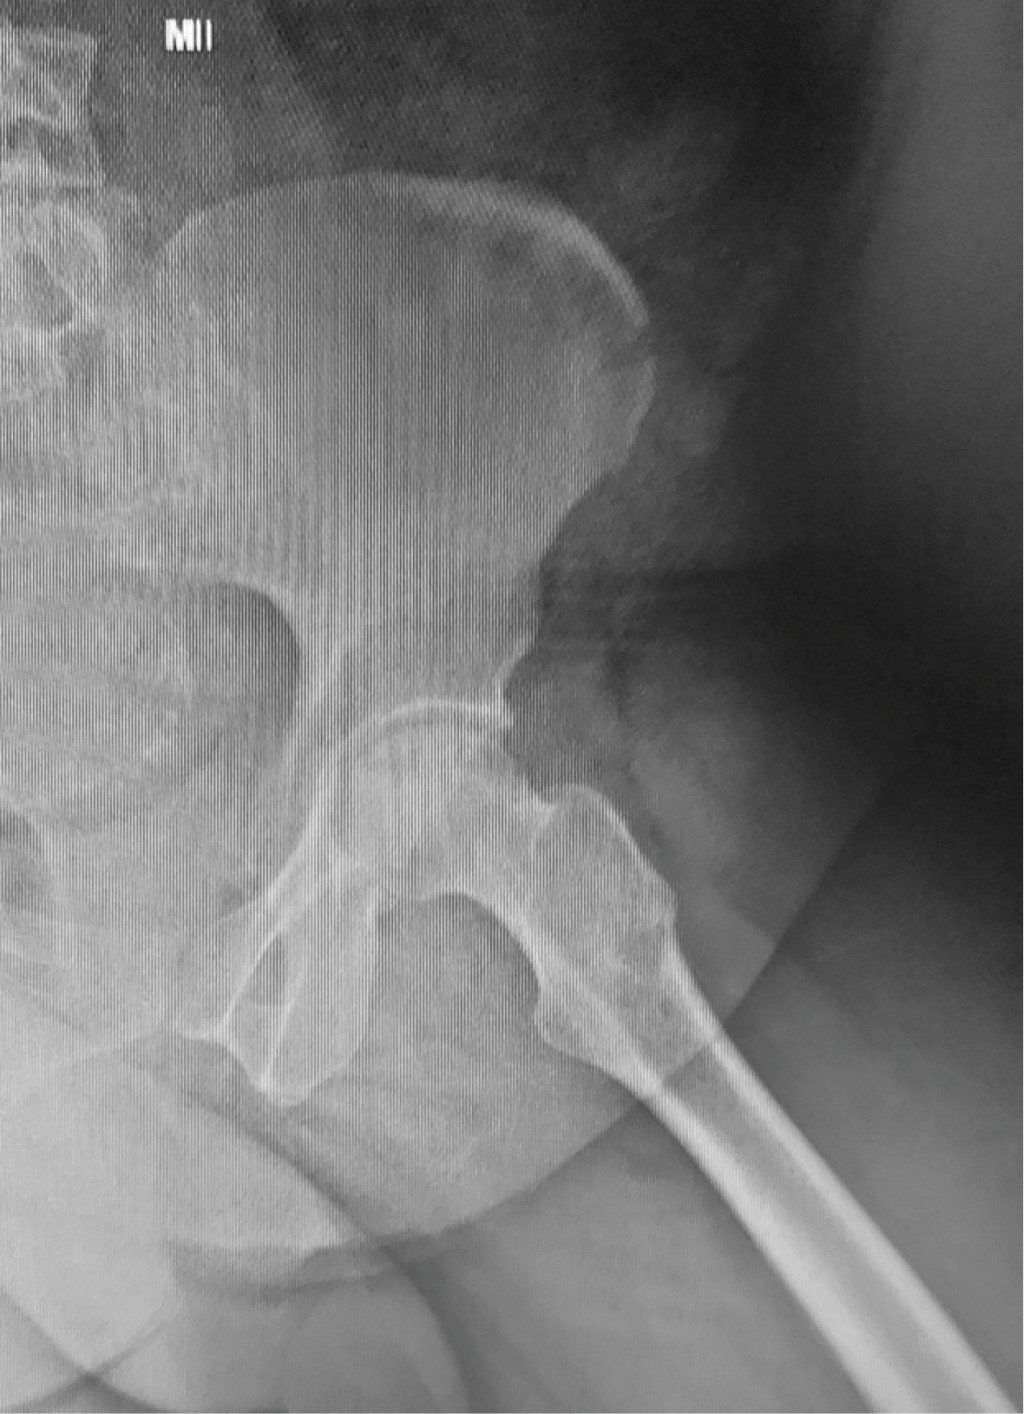

La técnica quirúrgica utilizada fue la perforación o Forage del núcleo cefálico, sobre mesa ortopédica bajo intensificador de imágenes (imagen en dos planos). Se introdujo una aguja guía hasta la zona de osteonecrosis. El orificio de inicio sobre la cortical externa del fémur se realizó a nivel del trocánter menor para evitar fracturas por estrés del fémur. A través de la aguja guía se introdujo una broca canulada de 9 mm de diámetro hasta llegar a 5 mm del cartílago articular (Figura 3). En todos los casos se obtuvo una muestra ósea para biopsia que confirmó el diagnóstico. Para la suplementación con ACMO, se obtuvo la muestra de zona dadora –cresta ilíaca– en forma percutánea, para posterior filtrado con utilización del sistema RegenKit BMC, Stryker, USA (Figuras 4 y 5).

En los casos restantes, no se observó progresión adicional del daño de la cabeza femoral, logrando así una supervivencia de 85.4% (Figuras 6 y 7).